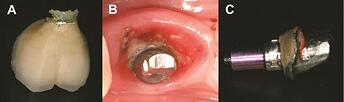

Mechanical treatments of peri-implantitis:

Mechanical treatments of peri-implantitis: ( A ) plastic curettes, ( B ) air abrasive, and ( C ) metallic brush. Reproduced from Ref. 34 under the Creative Commons Attribution License (CC BY 4.0) from Frontiers Media S.A.